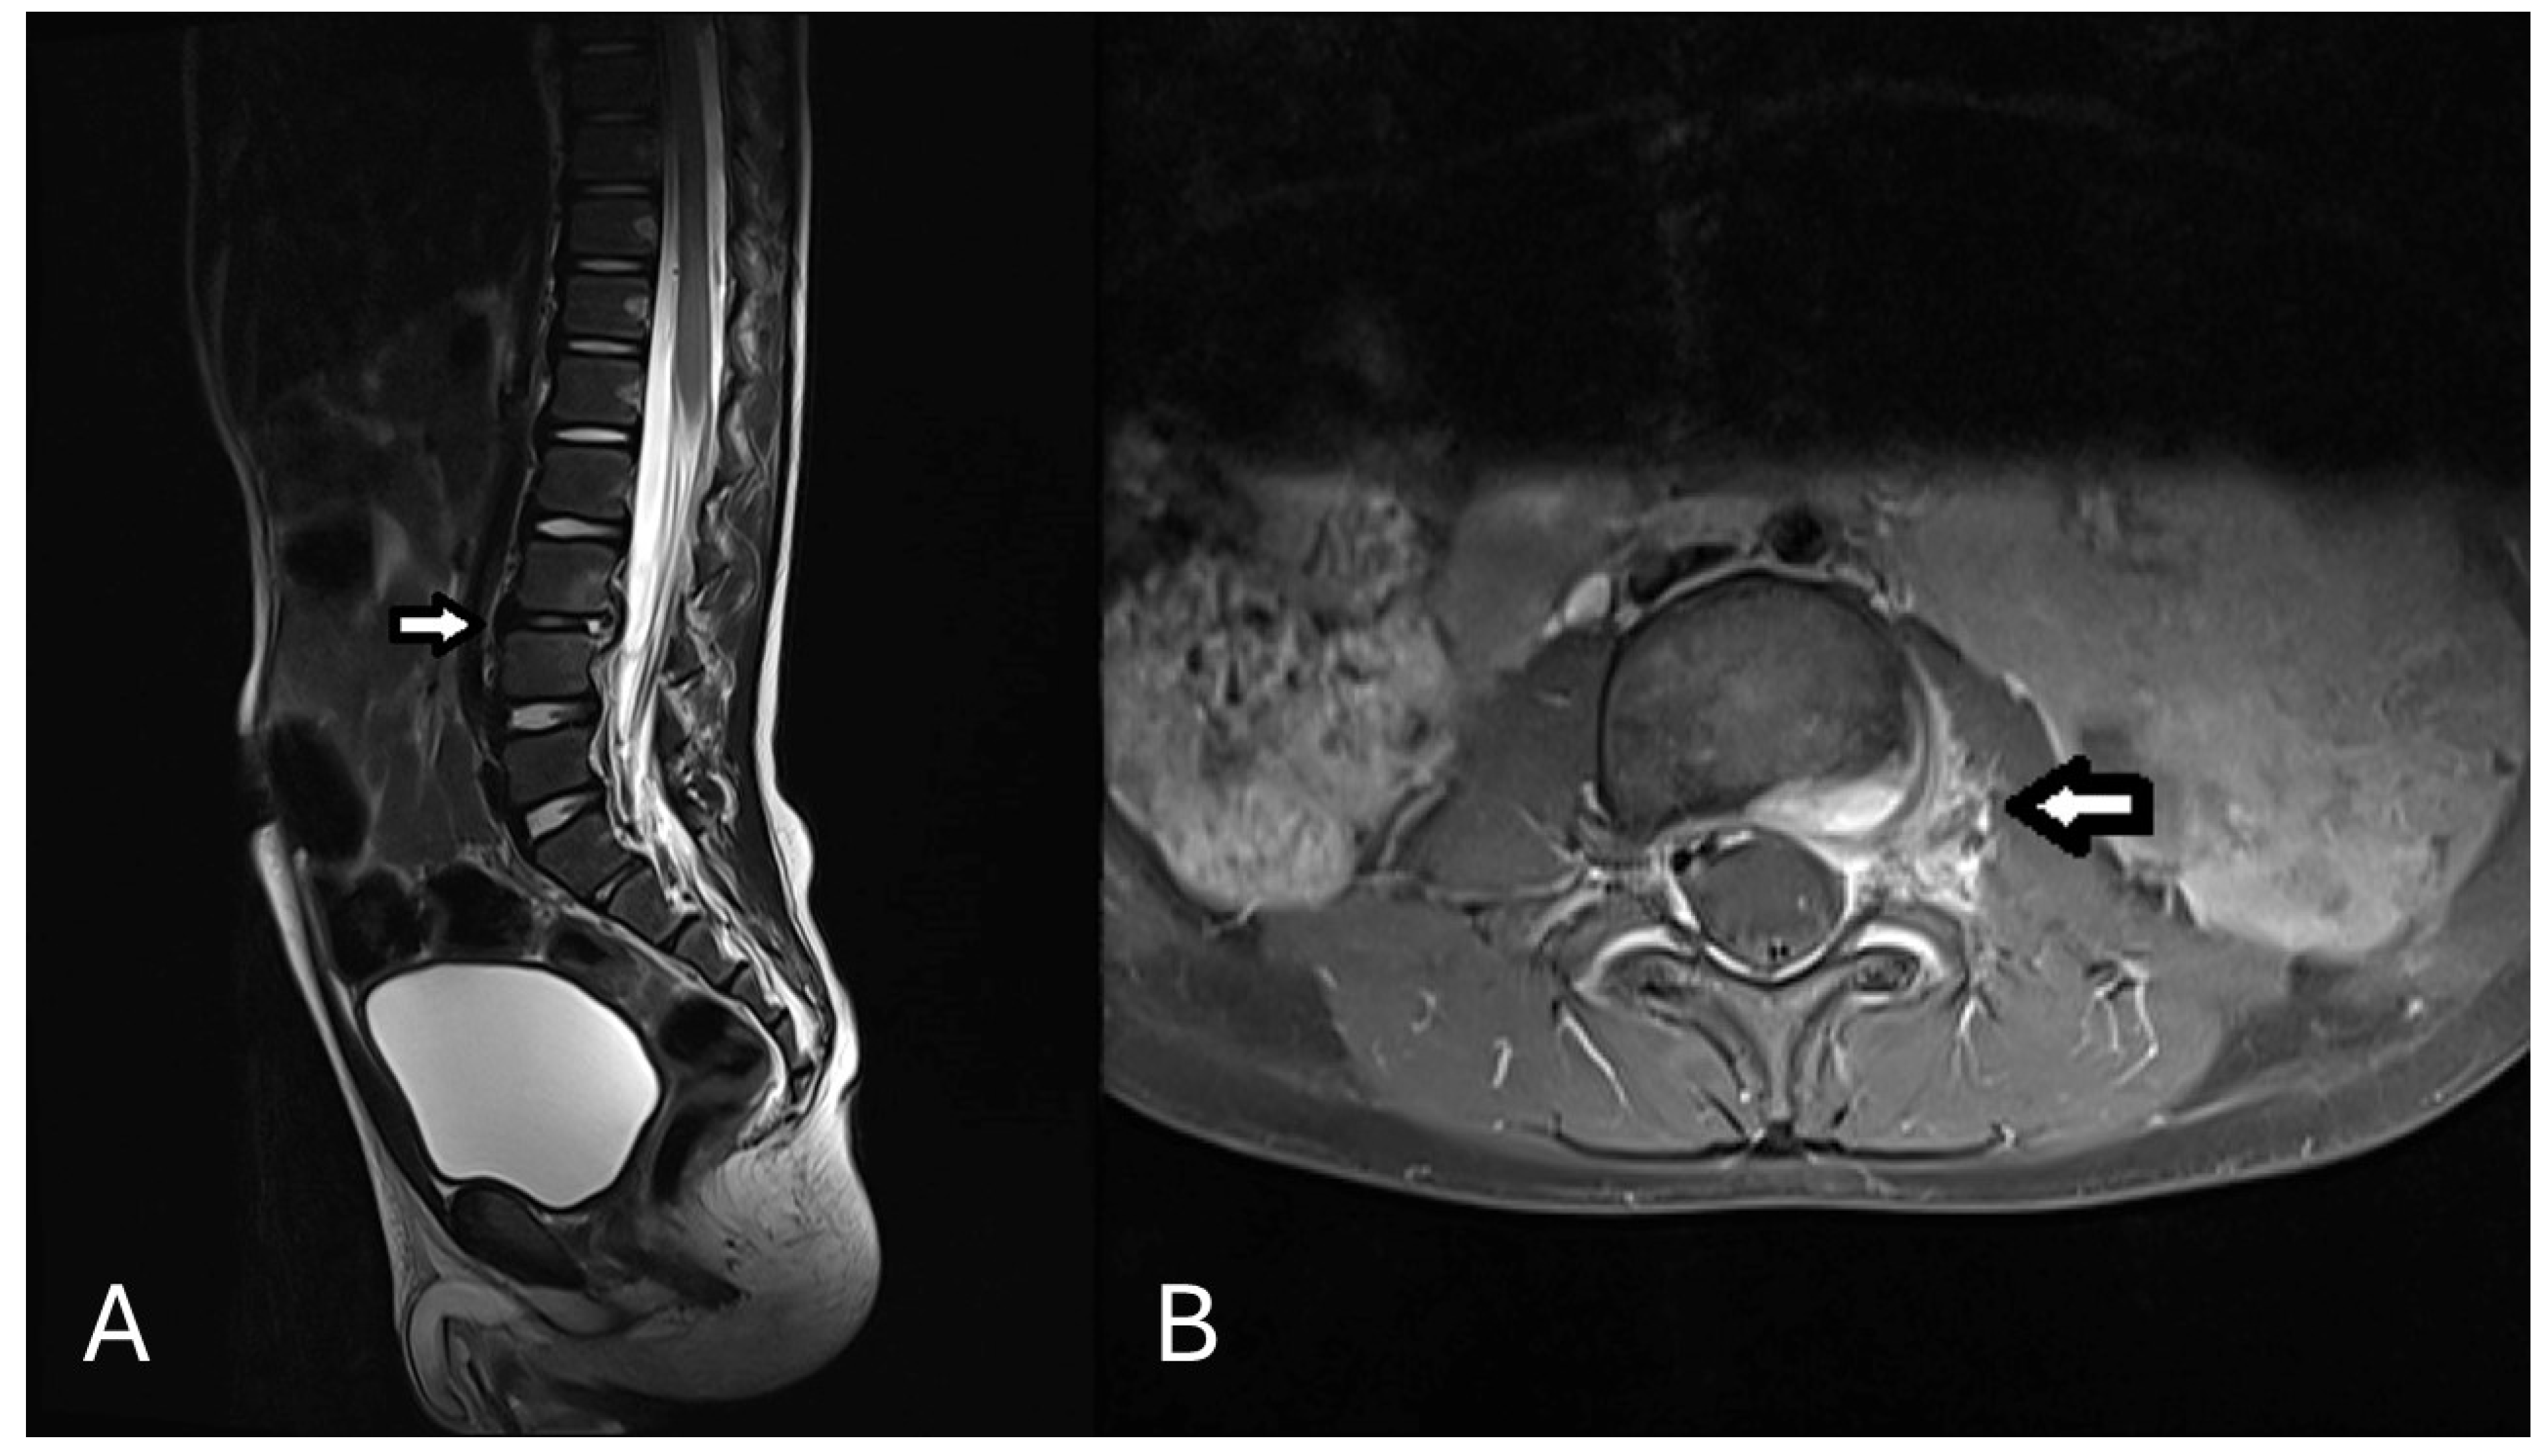

2. Case Presentation